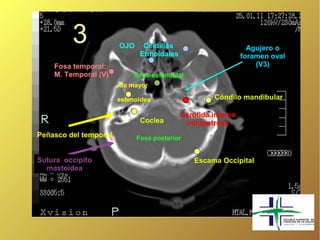

3               OJO

3             OJO     Celdillas

Etmoidales

Agujero o

foramen oval

Fosa temporal:                                                (V3)

M. Temporal (V)         Seno esfenoidal

Ala mayor

esfenoides                   Cóndilo mandibular

Carótida interna

Coclea        intrapetrosa

Peñasco del temporal         Fosa posterior

Sutura occipito                                Escama Occipital

mastoidea

3 OJO Celdillas Etmoidales Agujero o foramen oval Fosa temporal: (V3) M. Temporal (V) Seno esfenoidal Ala mayor esfenoides Cóndilo mandibular Carótida interna Coclea intrapetrosa Peñasco del temporal Fosa posterior Sutura occipito Escama Occipital mastoidea